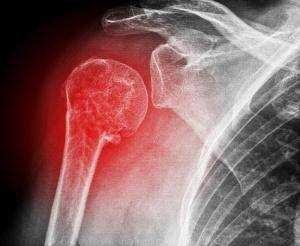

Перелом шейки плечевой кости, боковой части лопатки или ключицы

Все кости на рентгене отображаются в виде плотных белых образований. Переломы костей, а также трещины на них выглядят на снимках как тёмные полосы, расположенные в различных направлениях и имеющие различную локализацию и размер. Фото-рентген плечевого сустава позволяет обнаружить наличие переломов плечевой кости, ключицы и лопатки. Снимок нужен для того, чтобы определить сложность перелома, увидеть, как расположены осколки костей (если имеет место раздробление).